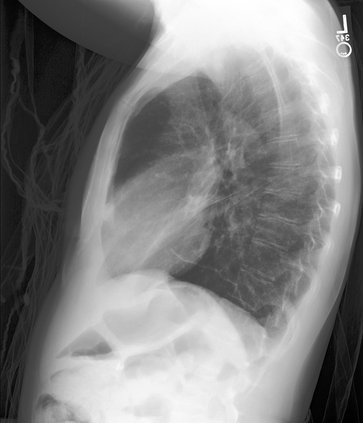

The latest breakthroughs in large vision-language models, such as Bard and GPT-4, have showcased extraordinary abilities in performing a wide range of tasks. Such models are trained on massive datasets comprising billions of public image-text pairs with diverse tasks. However, their performance on task-specific domains, such as radiology, is still under-investigated and potentially limited due to a lack of sophistication in understanding biomedical images. On the other hand, conversational medical models have exhibited remarkable success but have mainly focused on text-based analysis. In this paper, we introduce XrayGPT, a novel conversational medical vision-language model that can analyze and answer open-ended questions about chest radiographs. Specifically, we align both medical visual encoder (MedClip) with a fine-tuned large language model (Vicuna), using a simple linear transformation. This alignment enables our model to possess exceptional visual conversation abilities, grounded in a deep understanding of radiographs and medical domain knowledge. To enhance the performance of LLMs in the medical context, we generate ~217k interactive and high-quality summaries from free-text radiology reports. These summaries serve to enhance the performance of LLMs through the fine-tuning process. Our approach opens up new avenues the research for advancing the automated analysis of chest radiographs. Our open-source demos, models, and instruction sets are available at: https://github.com/mbzuai-oryx/XrayGPT.